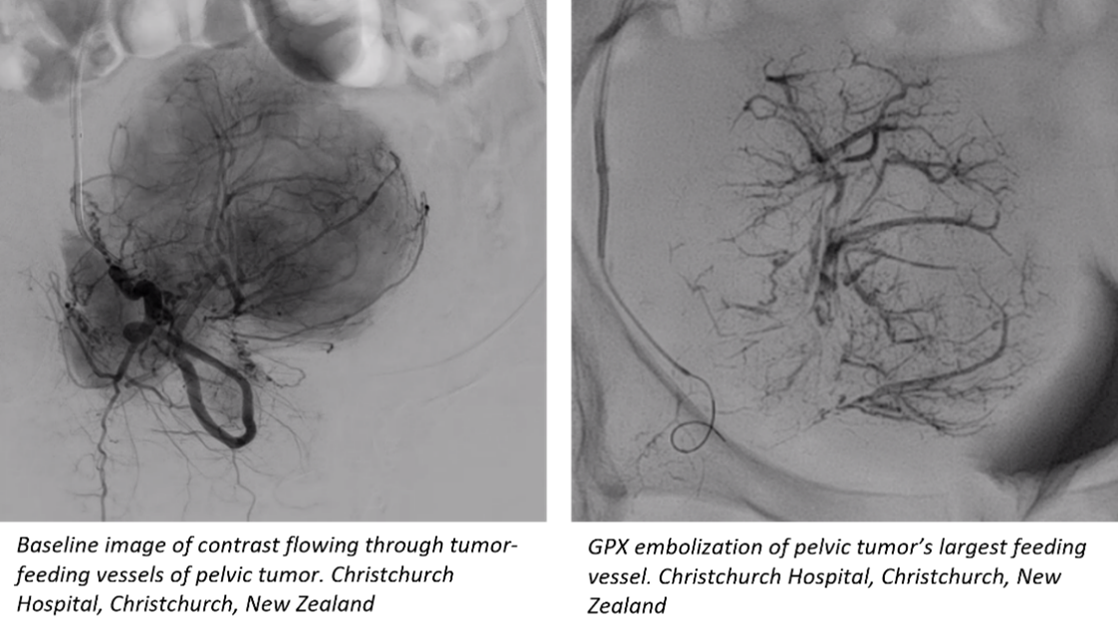

Fluidx Medical announces completion of trial enrollment for its novel embolic device, GPX. In this multi-center trial, GPX was used to treat a variety of primary and metastatic tumors, renal adenoma tumors, and a range of other arterial and venous applications.

GPX has shown promising results for tumor embolization and other uses where there is a desire for distal vessel bed penetration. Embolization is a procedure in which arterial or venous blood supply to an organ, malformation, aneurysm, bleed, tumor, and/or other abnormal area of issue is blocked. Interim results of the GPX study have been presented at recent annual congresses including Global Embolization Symposium & Technologies (GEST), Society of Interventional Radiology (SIR), and Leipzig Interventional Course (LINC).

GPX® is an innovative embolic designed for simple preparation and controllable material delivery. The device is packaged ready-to-use in a syringe, can be prepped tableside by the clinician in about 30 seconds, and may be delivered through standard microcatheters (no complex mixing systems or special delivery catheters are necessary). GPX technology is a low viscosity, aqueous-based solution in a syringe that solidifies into a durable embolus upon delivery without polymerization or dimethyl-sulfoxide (DMSO) precipitation.*